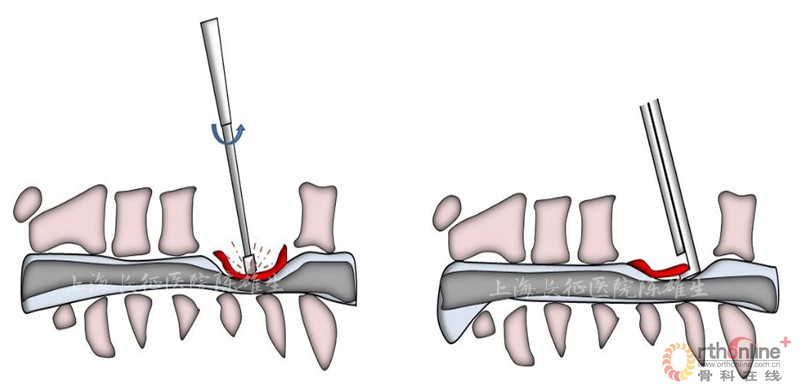

2.1枪钳对脊髓反复多次直接压迫

突出的椎间盘组织质地软,随着枪钳置入可发生形变,缓冲枪钳对脊髓压迫(图4)。而骨化物质地硬,随着枪钳置入不可发生形变,造成枪钳直接对脊髓造成二次压迫(图5)。

图4

图5